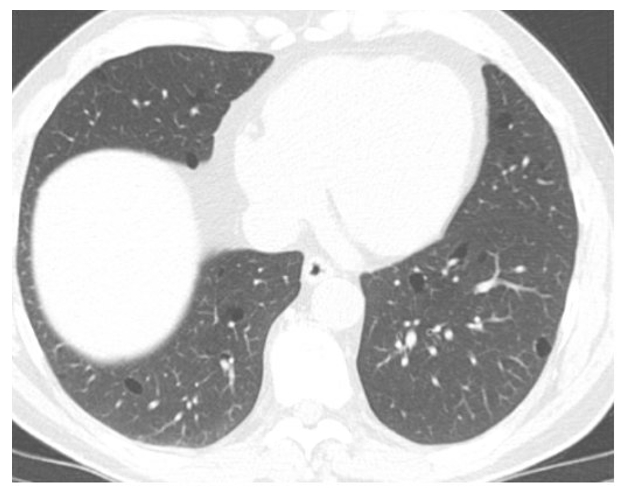

A 56-year-old male with a history of “holiday heart syndrome” presented for an AF consultation. Despite alcohol cessation, he continued to have paroxysmal AF with severe fatigue and palpitations. After three unsuccessful cardioversions and refractory episodes despite Dronedarone therapy, he was scheduled for an ablation. A pre-procedural transesophageal echocardiogram showed a left ventricular (LV) ejection fraction of 55%, mild concentric LV hypertrophy, and mild left atrial enlargement. These enlargements were new compared with imaging one year prior. A cardiac gated CT detailed the pulmonary vein structure and incidentally revealed bilateral cystic lung changes, leading to a pulmonology referral. Despite an initial successful ablation targeting the pulmonary vein, his symptoms returned within days. He was loaded with amiodarone. Monitoring on his apple watch showed a high burden of AF. He underwent a repeat ablation to achieve complete pulmonary vein isolation with improvement in his symptoms. Further pulmonary evaluation highlighted a family history of spontaneous pneumothorax and a dermatology consultation then confirmed BHDS via fibrofolliculoma biopsy.